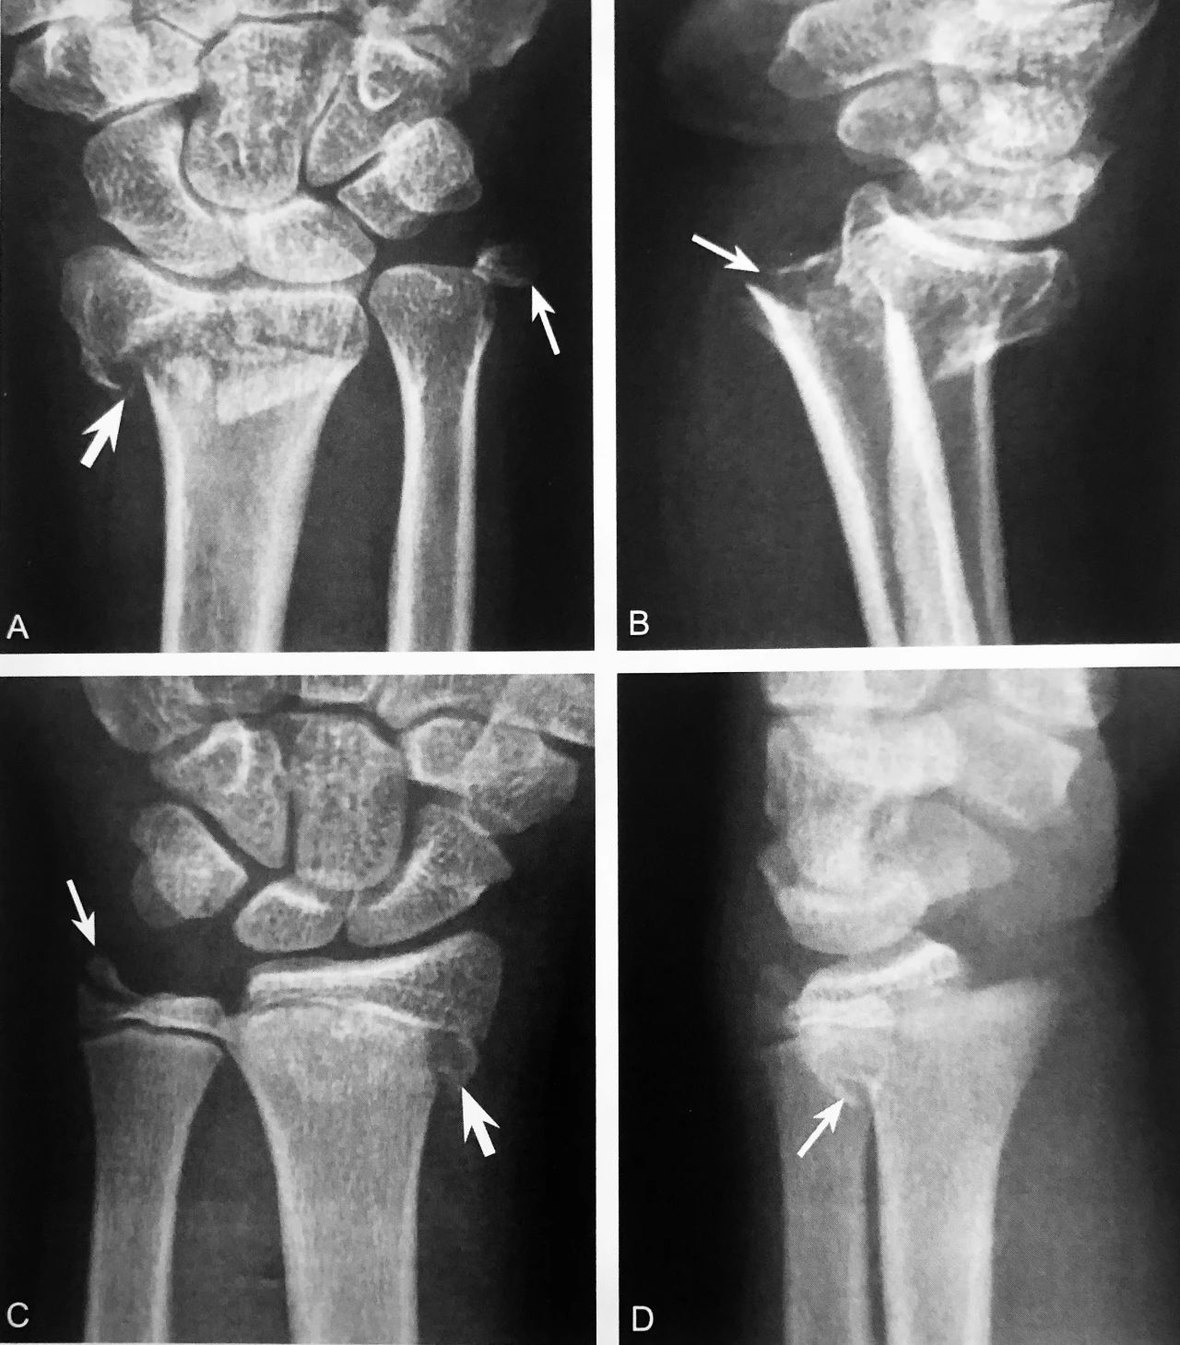

A.CT 横轴位图像,正常椎弓峡部层面骨性椎管呈完整环状结构,前部为椎体后缘,两侧为椎弓根序连于椎板,后部为棘突基底部围成;B.环裂征:双侧椎弓峡部崩裂(箭头),裂隙横跨峡部,断裂面形态不规则

判读要点:

1、椎弓峡部裂特征性直接征象;

2、在椎弓峡部平面 CT 横断位观察,以 RGCT 图像观察最佳;3、诊断时需除外脊椎裂、椎体畸形(蝴蝶椎)和手术椎板切除。